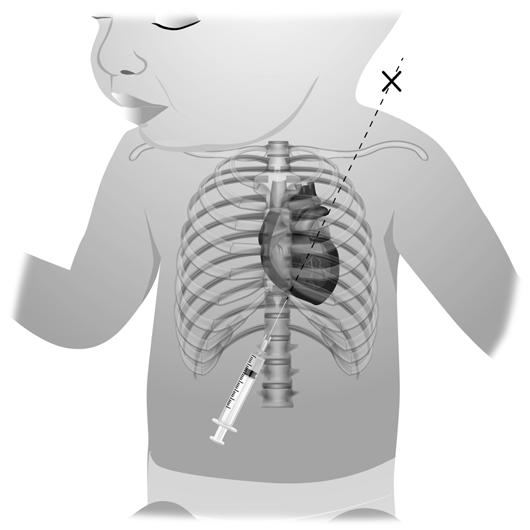

Local de inserção:

■ 2.º espaço intercostal da linha médio-clavicular (Figura 9.1.2);

■ 4.º a 6.º espaços intercostais da linha médio-axilar (bordo superior da costela inferior).

Adaptado de Oliveira et al. (s.d.).

Figura 9.1.2 – Local de inserção.